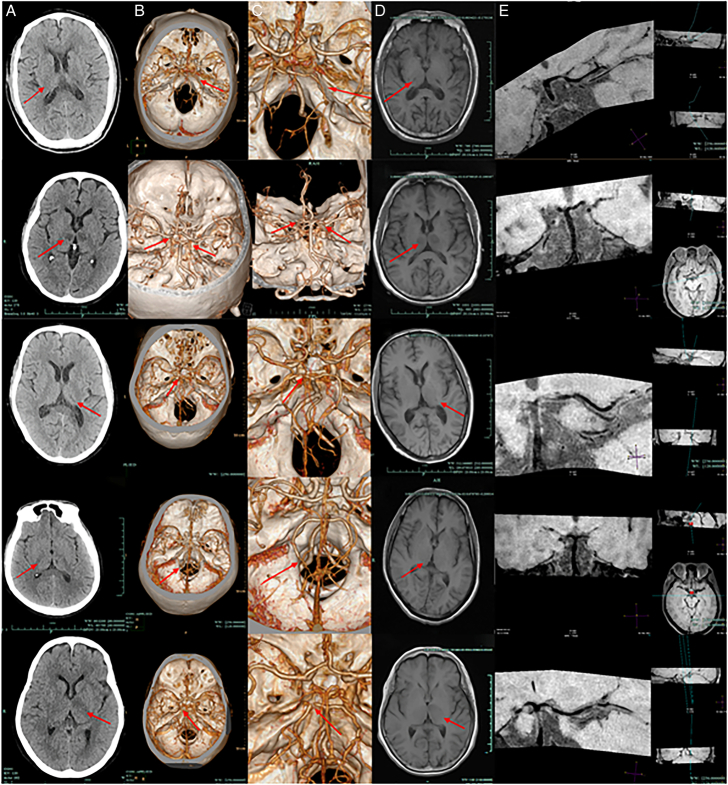

Introduction: Ten patients with thalamic infarction caused by moderate-to-severe posterior cerebral artery (PCA) stenosis confirmed by computed tomography angiography (CTA) were enrolled. To better assess the vascular pathology, high-resolution magnetic resonance imaging (HRMRI) was subsequently used to evaluate the PCA in detail. In addition, we retrospectively analyzed clinical features, treatments, and prognostic outcomes.

Case report: Ten patients were included, 7 males and 3 females, with an average age of 67.8±6.6 years. Past history includes: smoking (50%), drinking (30%), hypertension (70%), diabetes mellitus (40%), hyperlipidemia (10%), and cerebral infarction (10%). Clinical manifestations include sensory disorders (60%), motor disorders (50%), cognitive and consciousness disorders (10%), and language impairment (20%). HRMRI suggested that the PCA was moderately or severely stenosed in 4 cases, mildly stenosed in 5 cases, and normal in 1 case. It also suggested the presence of PCA atherosclerotic plaques in 9 patients.

Conclusion: Antiplatelet therapy proves effective for this patient population. HRMRI identified atherosclerotic plaques mainly in the PCA's P1 and P2 segments. P1 stenosis often impairs consciousness, while P2 stenosis typically causes sensory/motor deficits. HRMRI aids in evaluating stenosis and plaque features for diagnosis and treatment guidance.